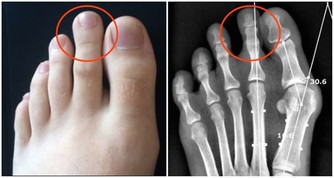

便秘造成的憩室,是大腸藏汙納垢的溫床  有些人在用力排便時,腸子因為壓力的關係,讓結腸壁較脆弱的地方像吹氣球一樣長出一個氣囊出來,就形成了憩室。它是一種良性的囊袋,是大腸最容易藏汙納垢的地方,如果不處理,久而久之就有形成大腸癌的可能。

憩室一旦長出來就不易消除,老人家和便秘者有百分之三十到四十的人都會有憩室,平時不痛不癢,就像盲腸一樣,如果沒有髒東西跑進去就沒事,但如果排泄物囤積其中,就容易發生感染或發炎。因此,已經有憩室的人應以斷食、灌腸來定期清除裡面的髒東西。